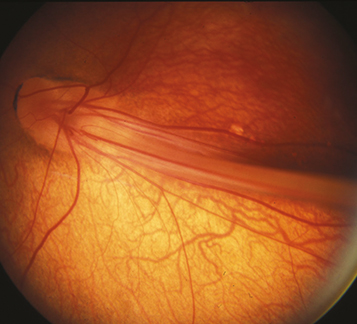

(See Figure 8.3.1.)

Figure 8.3.1: Familial exudative vitreoretinopathy with a falciform fold.

Vascular dragging and peripheral retinal nonperfusion, most prominently temporally, although can extend 360 degrees. Bilateral but often asymmetric. Peripheral retinal vessels have a fimbriated border. Present at birth.

Peripheral neovascularization and/or fibrovascular proliferation at the border of vascular and avascular retina; temporal dragging of macula through contraction of fibrovascular tissue; radial retinal folds; vitreous hemorrhage; epiretinal membranes; tractional, exudative, and/or rhegmatogenous retinal detachment; peripheral intraretinal and subretinal lipid exudation. May  present with strabismus or leukocoria in childhood. Cataract, band keratopathy, neovascular glaucoma, or phthisis possible.